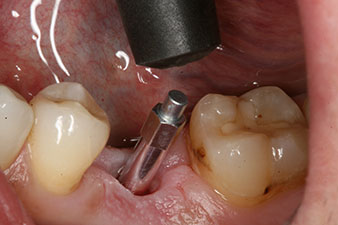

The implant was uncovered two months later and a gingiva former was screwed in (no picture).

After healing of the soft tissue, the implant stability was measured again before delivery of the prosthetic restoration.